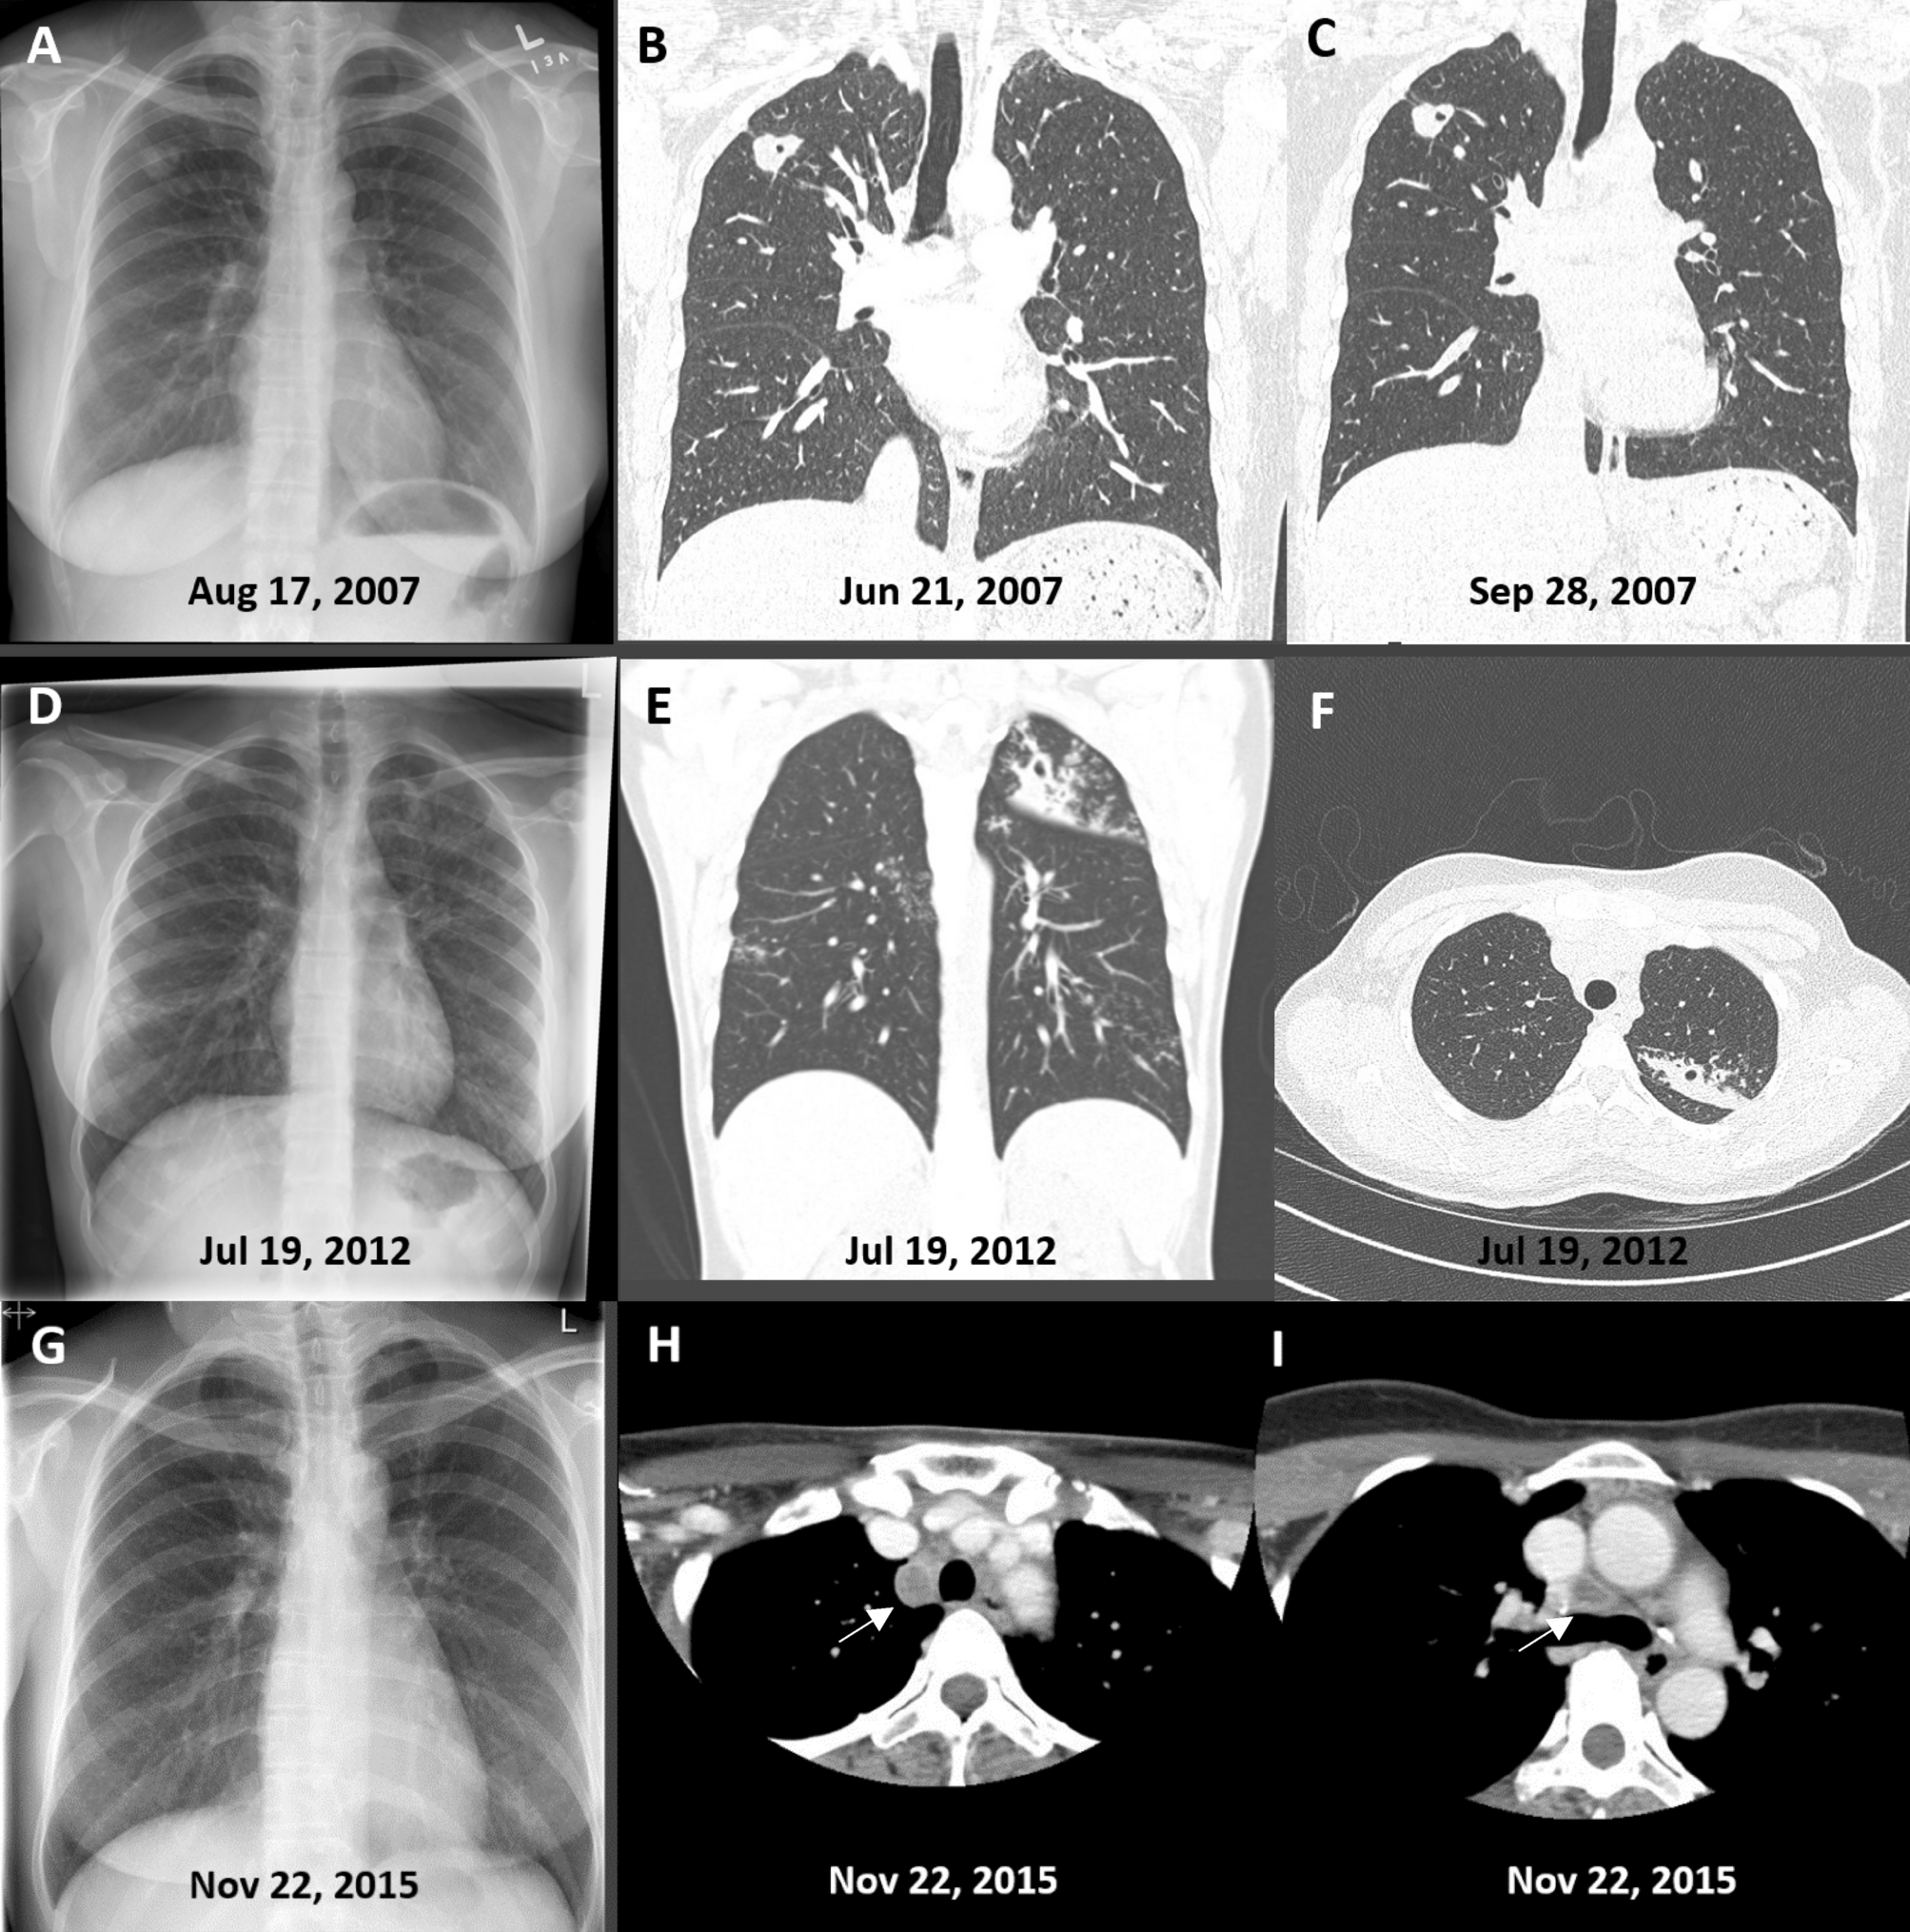

Figure 2

(A,B,C) Frontal chest radiograph (A) and thin Sect. (1.0 mm) coronal reformat computed tomographic (CT) images (B and C) in a patient diagnosed with smear-negative, culture-positive subclinical pulmonary tuberculosis on August 28, 2007. A small cavity is visible on CT scan but not on chest radiograph; the abnormality in the right upper lobe is stable over several months. (D,E,F) Frontal chest radiograph (D), a multiplanar reformation (MPR) coronal CT image (3 mm) (E) and a 1 mm transverse CT image through the upper thorax (F) in a patient diagnosed with smear-negative, culture-positive subclinical pulmonary tuberculosis on July 26, 2012. Cavitation is visible on CT scan but not on chest radiograph; endobronchial spread is more visible on CT scan than on chest radiograph. (G,H,I) Frontal chest radiograph (G) and 3 mm transverse CT images at the level of the aortic arch (H) and main carina (I) in a patient diagnosed with smear-positive, culture-positive subclinical pulmonary tuberculosis on November 24, 2015. An enlarged, centrally necrotic, lymph node is visible in the right paratracheal area (H) and a borderline enlarged centrally necrotic lymph node is visible just anterior to the main carina (I) on CT scan; neither was clearly visible or reported on chest radiograph.